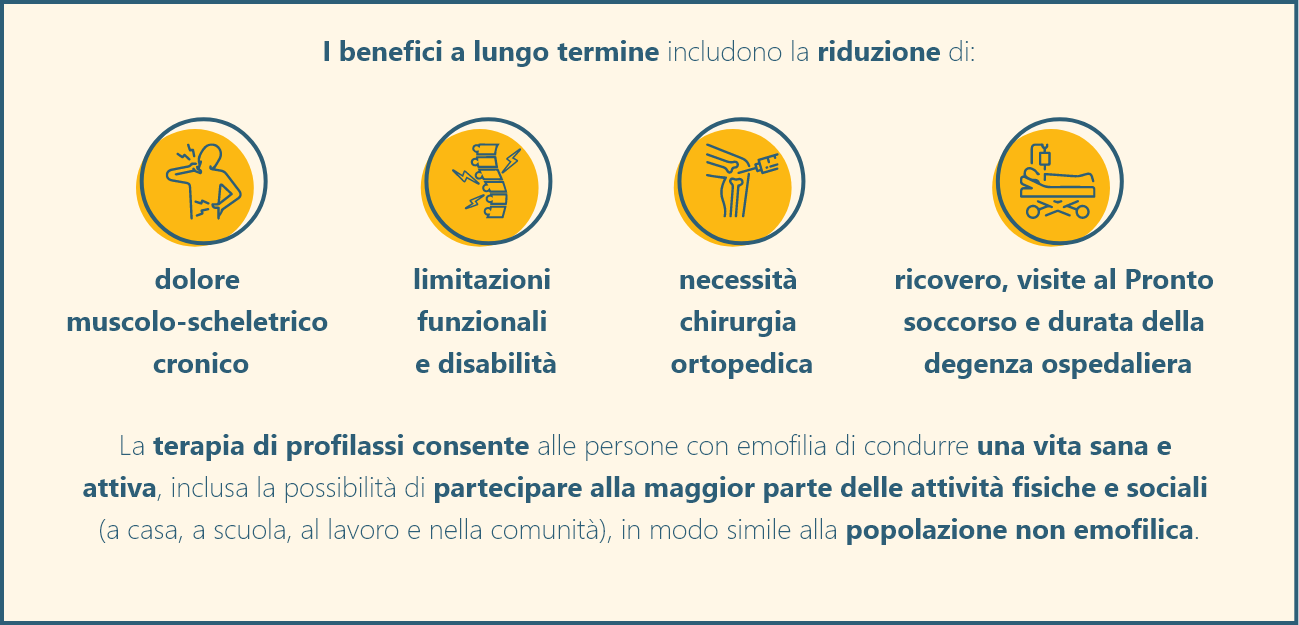

La profilassi consiste in infusioni regolari di fattore per prevenire i sanguinamenti e i microsanguinamenti e si ritiene che sia il modo più efficace per raggiungere questo obiettivo. Dovrebbe iniziare in tenera età e prima del primo sanguinamento.

La profilassi fornisce vantaggi superiori rispetto alla terapia on-demand.